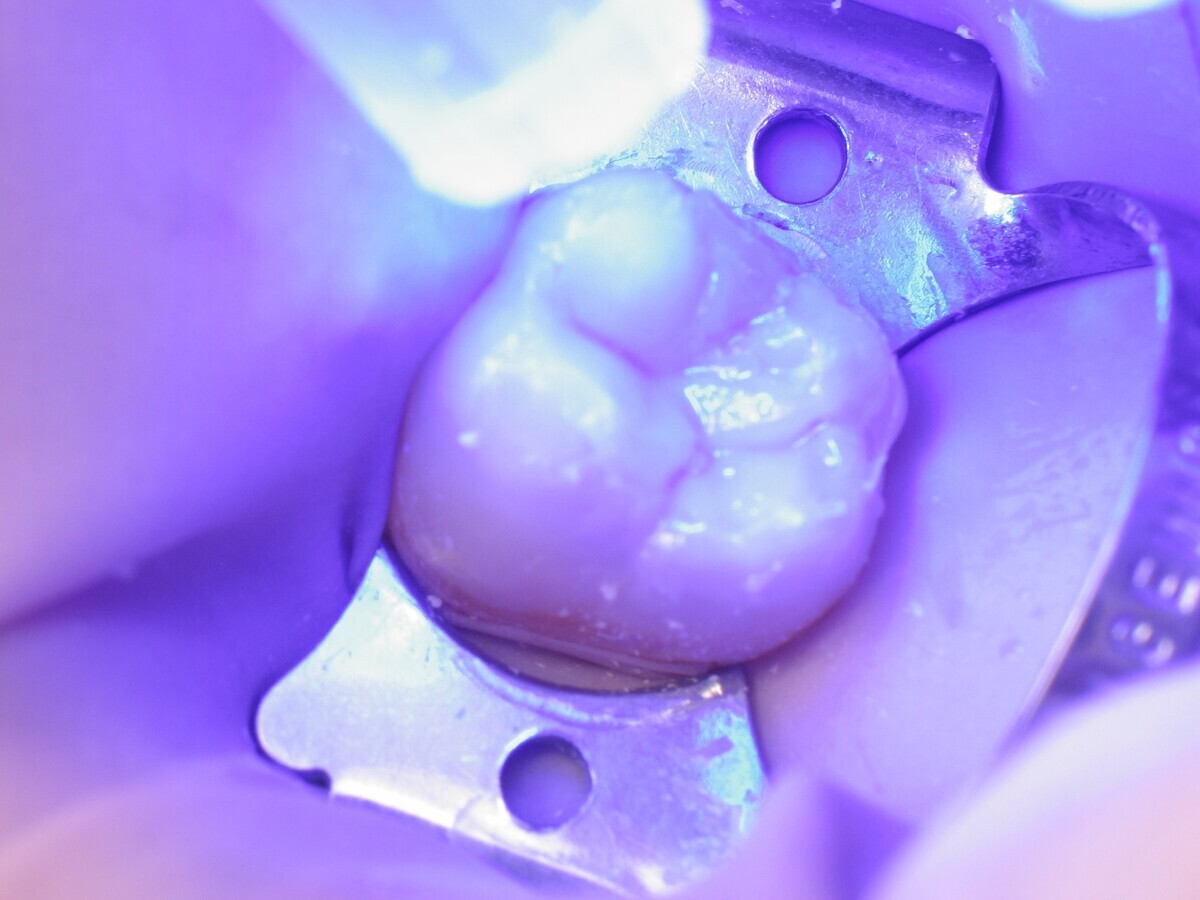

Este artículo describe el tratamiento de una cavidad clase I en un molar utilizando un composite termoviscoso mediante la técnica de la almohadilla (Figura 1). En primer lugar, se registran los detalles anatómicos utilizando una resina transparente, fluida y fotopolimerizable (Clip Flow, VOCO). El diente se aísla con un dique antes de aplicar el composite transparente a la superficie oclusal con un cepillo aplicador y fotopolimerizar durante 10 segundos (Figuras 2-4). La almohadilla oclusal así obtenida (Figura 5) debe almacenarse en alcohol (etanol o isopropanol) para eliminar la capa de inhibición. Luego se limpia la cavidad clase I (Figuras 6 y 7). A continuación se graba el esmalte durante 30 segundos y la dentina durante 15 segundos (Conditioner 36, Dentsply Sirona) y luego se enjuaga bien (Figuras 8 a 10). Debido al bajo espesor de la dentina remanente, también se aplica protección pulpar (Telio Desensitizer, Ivoclar Vivadent) (Figura 11). Luego se frota el adhesivo sobre las superficies dentales durante 20 segundos (Futurabond DC, VOCO), luego se seca bajo una pulverización de aire sin aceite graso durante 5 segundos y luego se fotopolimeriza durante 10 segundos (Figuras 12, 13). Para una humectación óptima, el fondo de la cavidad se cubre con un compuesto fluido de baja viscosidad (GrandioSO Light Flow, A3.5, VOCO) y se fotopolimeriza durante 20 segundos (Figuras 14, 15). Utilizando el Dispensador VisCalor, un dispensador portátil que permite el calentamiento y la aplicación simultánea de resinas, la cavidad se llena luego con un composite termoviscoso bulk (VisCalor Bulk, A2, VOCO).

Figura 02. Instalación del dique.

Figura 03. Aplicación de Clip Flow con un pincel aplicador.

Figura 04. Fotopolimerización de Clip Flow.

Figura 05. Almohadilla oclusal.